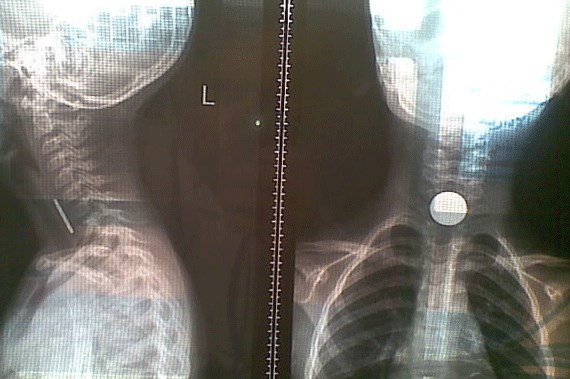

ومنذ عدة أيام، ساهمت سرعة تجاوب أهل من منطقة نجران مع طفلتهم وإسعافها في إنقاذ حياتها بعد ابتلاعها قطعة نقدية!

حيث نجح الفريق الطبي في مستشفى حبونا العام في منطقة نجران في استخراج قطعة معدنية علقت في مريء طفلة تبلغ من العمر خمس سنوات، حين أدخلها أهلها قسم الطوارئ وهي تعاني من تطريش وسعال، وحين الكشف عليها من قبل اختصاصية الأطفال، أجريت لها الإجراءات الأولية.

وأظهرت الأشعة وجود جسم غريب بالمريء، وبعد استدعاء اختصاصي الأنف والأذن والحنجرة، تم نقل الطفلة إلى قسم العمليات تحت التخدير العام وإجراء عملية جراحية لها تم من خلالها إخراج القطعة المعدنية "قطعة نقدية" من مريئها، تكللت ولله الحمد بالنجاح.